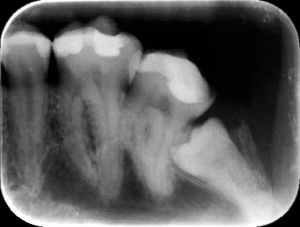

Коли зуб ріжеться і болить, треба зробити панорамний рентген. Він дає огляд щелепи. Видно, чи намічаються зустрічні зуби. Коли на протилежній щелепі зуба нема — можуть травмуватися ясна. Тому за такими має спостерігати стоматолог.

У деяких "вісімок" більш ніж три корені або непрохідні канали. Вони сильно закручені. Якщо почнеться запалення нервів, запломбувати їх дуже складно. Те саме — коли рот не відкривається, й до зуба неможливо дотягнутися. Все це можна побачити на знімку.